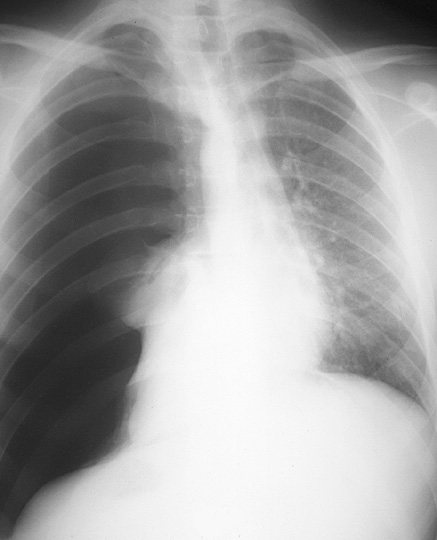

Gallery Blunt Chest Trauma Pneumothorax 3 tension

3 tension